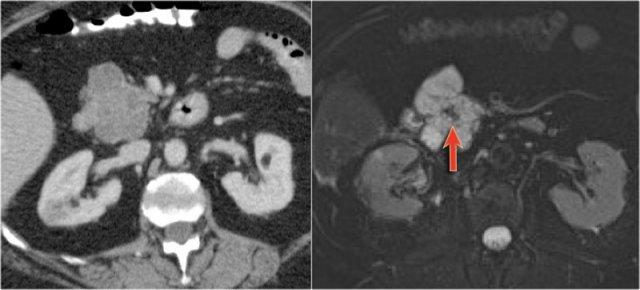

Hình ảnh CT của bệnh nhân nữ 46 tuổi với triệu chứng đau bụng phải mơ hồ.

Các đặc điểm hình ảnh bao gồm:

- Nang có vách ngăn kích thước 7 cm ở đầu tụy.

- Vỏ nang nhẵn.

- Không có thùy hóa (lobulation).

- Không thông với ống tụy chính.

MRI cho thấy nang có vách ngăn ở đầu tụy kích thước 7 cm với vỏ nang nhẵn, không có thùy hóa và không thông với ống tụy chính.

Kết quả phẫu thuật xác nhận u nang tuyến nhầy độ thấp (low grade mucinous cystadenoma) có mô đệm buồng trứng (ovarian stroma).

Hình ảnh CT của bệnh nhân nữ 30 tuổi có tiền sử viêm tụy do sỏi mật và đã cắt túi mật.

Bệnh nhân xuất hiện đau bụng trái đột ngột tăng nặng.

Siêu âm cho thấy tổn thương dạng nang tăng kích thước, được chẩn đoán là nang giả tụy (pseudocyst).

Tuy nhiên, CT cho thấy tổn thương dạng nang không có thùy hóa ở đuôi tụy với các vách ngăn bên trong có ngấm thuốc, không thông với ống tụy chính (hình).

Tiếp tục xem hình ảnh MRI…

Chuỗi xung T1W sau tiêm thuốc tương phản từ Gadolinium thể hiện rõ hơn các vách ngăn bên trong.

Phẫu thuật cắt đuôi tụy xác nhận u nang tuyến nhầy kích thước 14 cm có mô đệm buồng trứng (ovarian stroma).